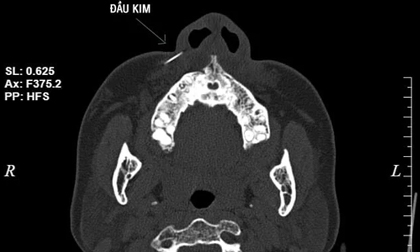

Sau khi thực hiện chụp CT scanner, các bác sĩ nhận thấy hình ảnh dị vật khoảng 1cm, vị trí phần mềm cánh mũi phải, chỉ định thủ thuật lấy dị vật. Sau 10’, đầu kim được lấy ra từ vùng má bệnh nhân.

Ảnh chụp CT scanner